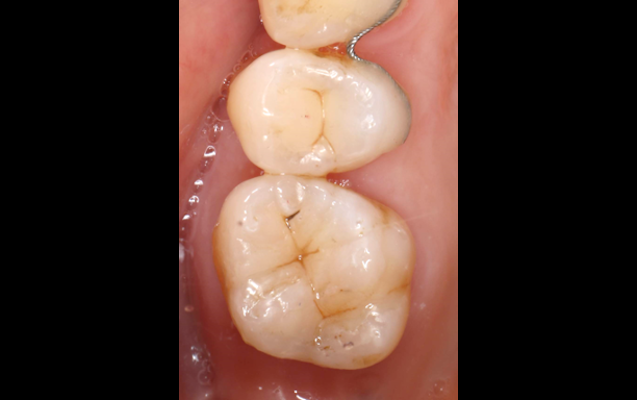

虫歯が範囲が狭い場合や治療済の金属を入れ替える場合、また患者様の健全な歯が多く残っている場合に最適な審美歯科治療です。

インレーは小さな虫歯、アンレーは中程度の虫歯に詰めるセラミックの詰め物のことで、歯の透明感や色を再現することが可能で、自然な仕上がりの審美性に高い治療方法となります。

(実際の症例)